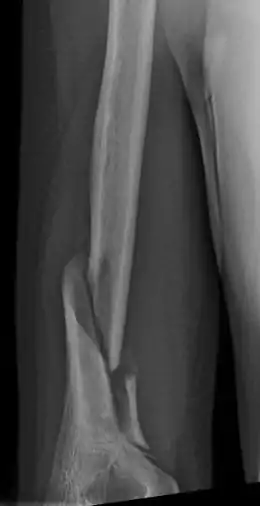

Holstein–Lewis fracture

A Holstein–Lewis fracture is a fracture of the distal third of the humerus resulting in entrapment of the radial nerve.

Holstein–Lewis fracture at 5 weeks post fracture